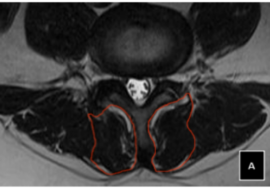

كيفية تشخيص أي مشكلة في العمود الفقري

عند زيارة الطبيب، يتم:

- فحص القوام والظهر

- تقييم التماثل بين الجانبين

- اختبار الانحناء

- طلب أشعة لتحديد درجة الانحناء عند الحاجة

- التمارين العلاجية: تقوية عضلات الظهر والبطن، تحسين التوازن العضلي، زيادة مرونة العمود الفقري.

- العلاج الطبيعي: برنامج متخصص لتحسين الوضعية بشكل تدريجي وآمن.